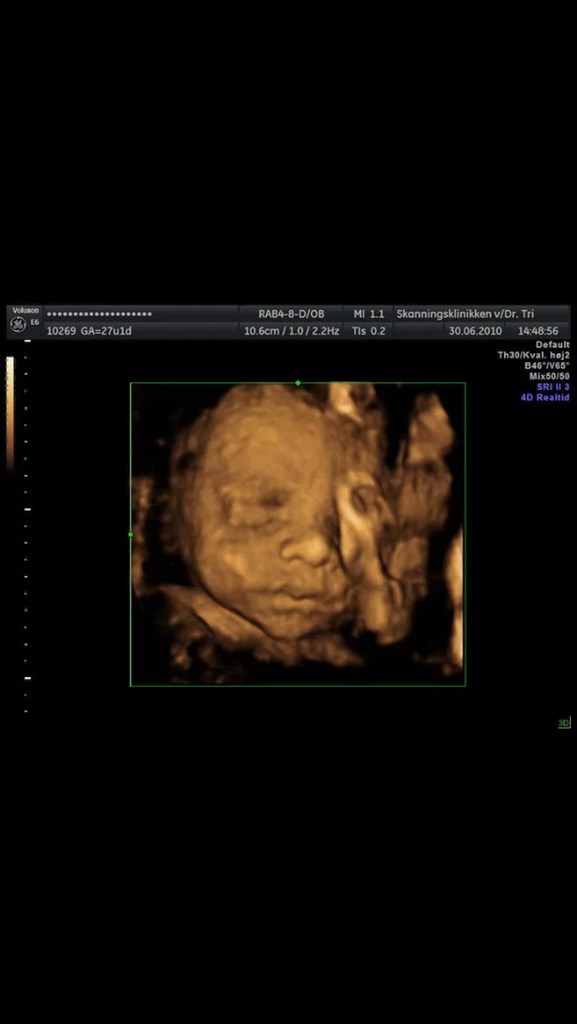

Søger man på Google kommer der kun 3D-billeder.

Så jeg vil høre om nogen herinde har et billede eller to fra uge 28 de vil vise? Og hvor lang var jeres baby, og fik I vægt at vide?